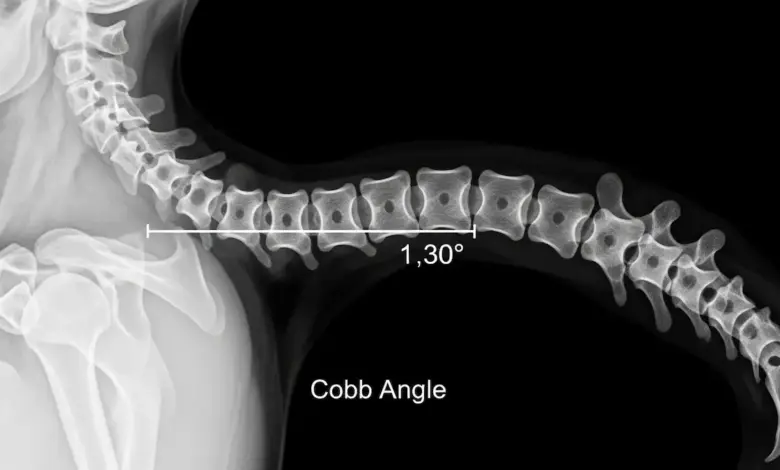

O exame mais usado para confirmar e quantificar é a radiografia da coluna, que permite medir o ângulo da curvatura, onde curvas torácicas acima do esperado para a idade podem caracterizar hipercifose.

Qual grau é considerado hipercifose?

Em geral, considera-se hipercifose quando a curva torácica está acima do intervalo esperado na radiografia. A confirmação depende da medida do ângulo e da avaliação clínica.